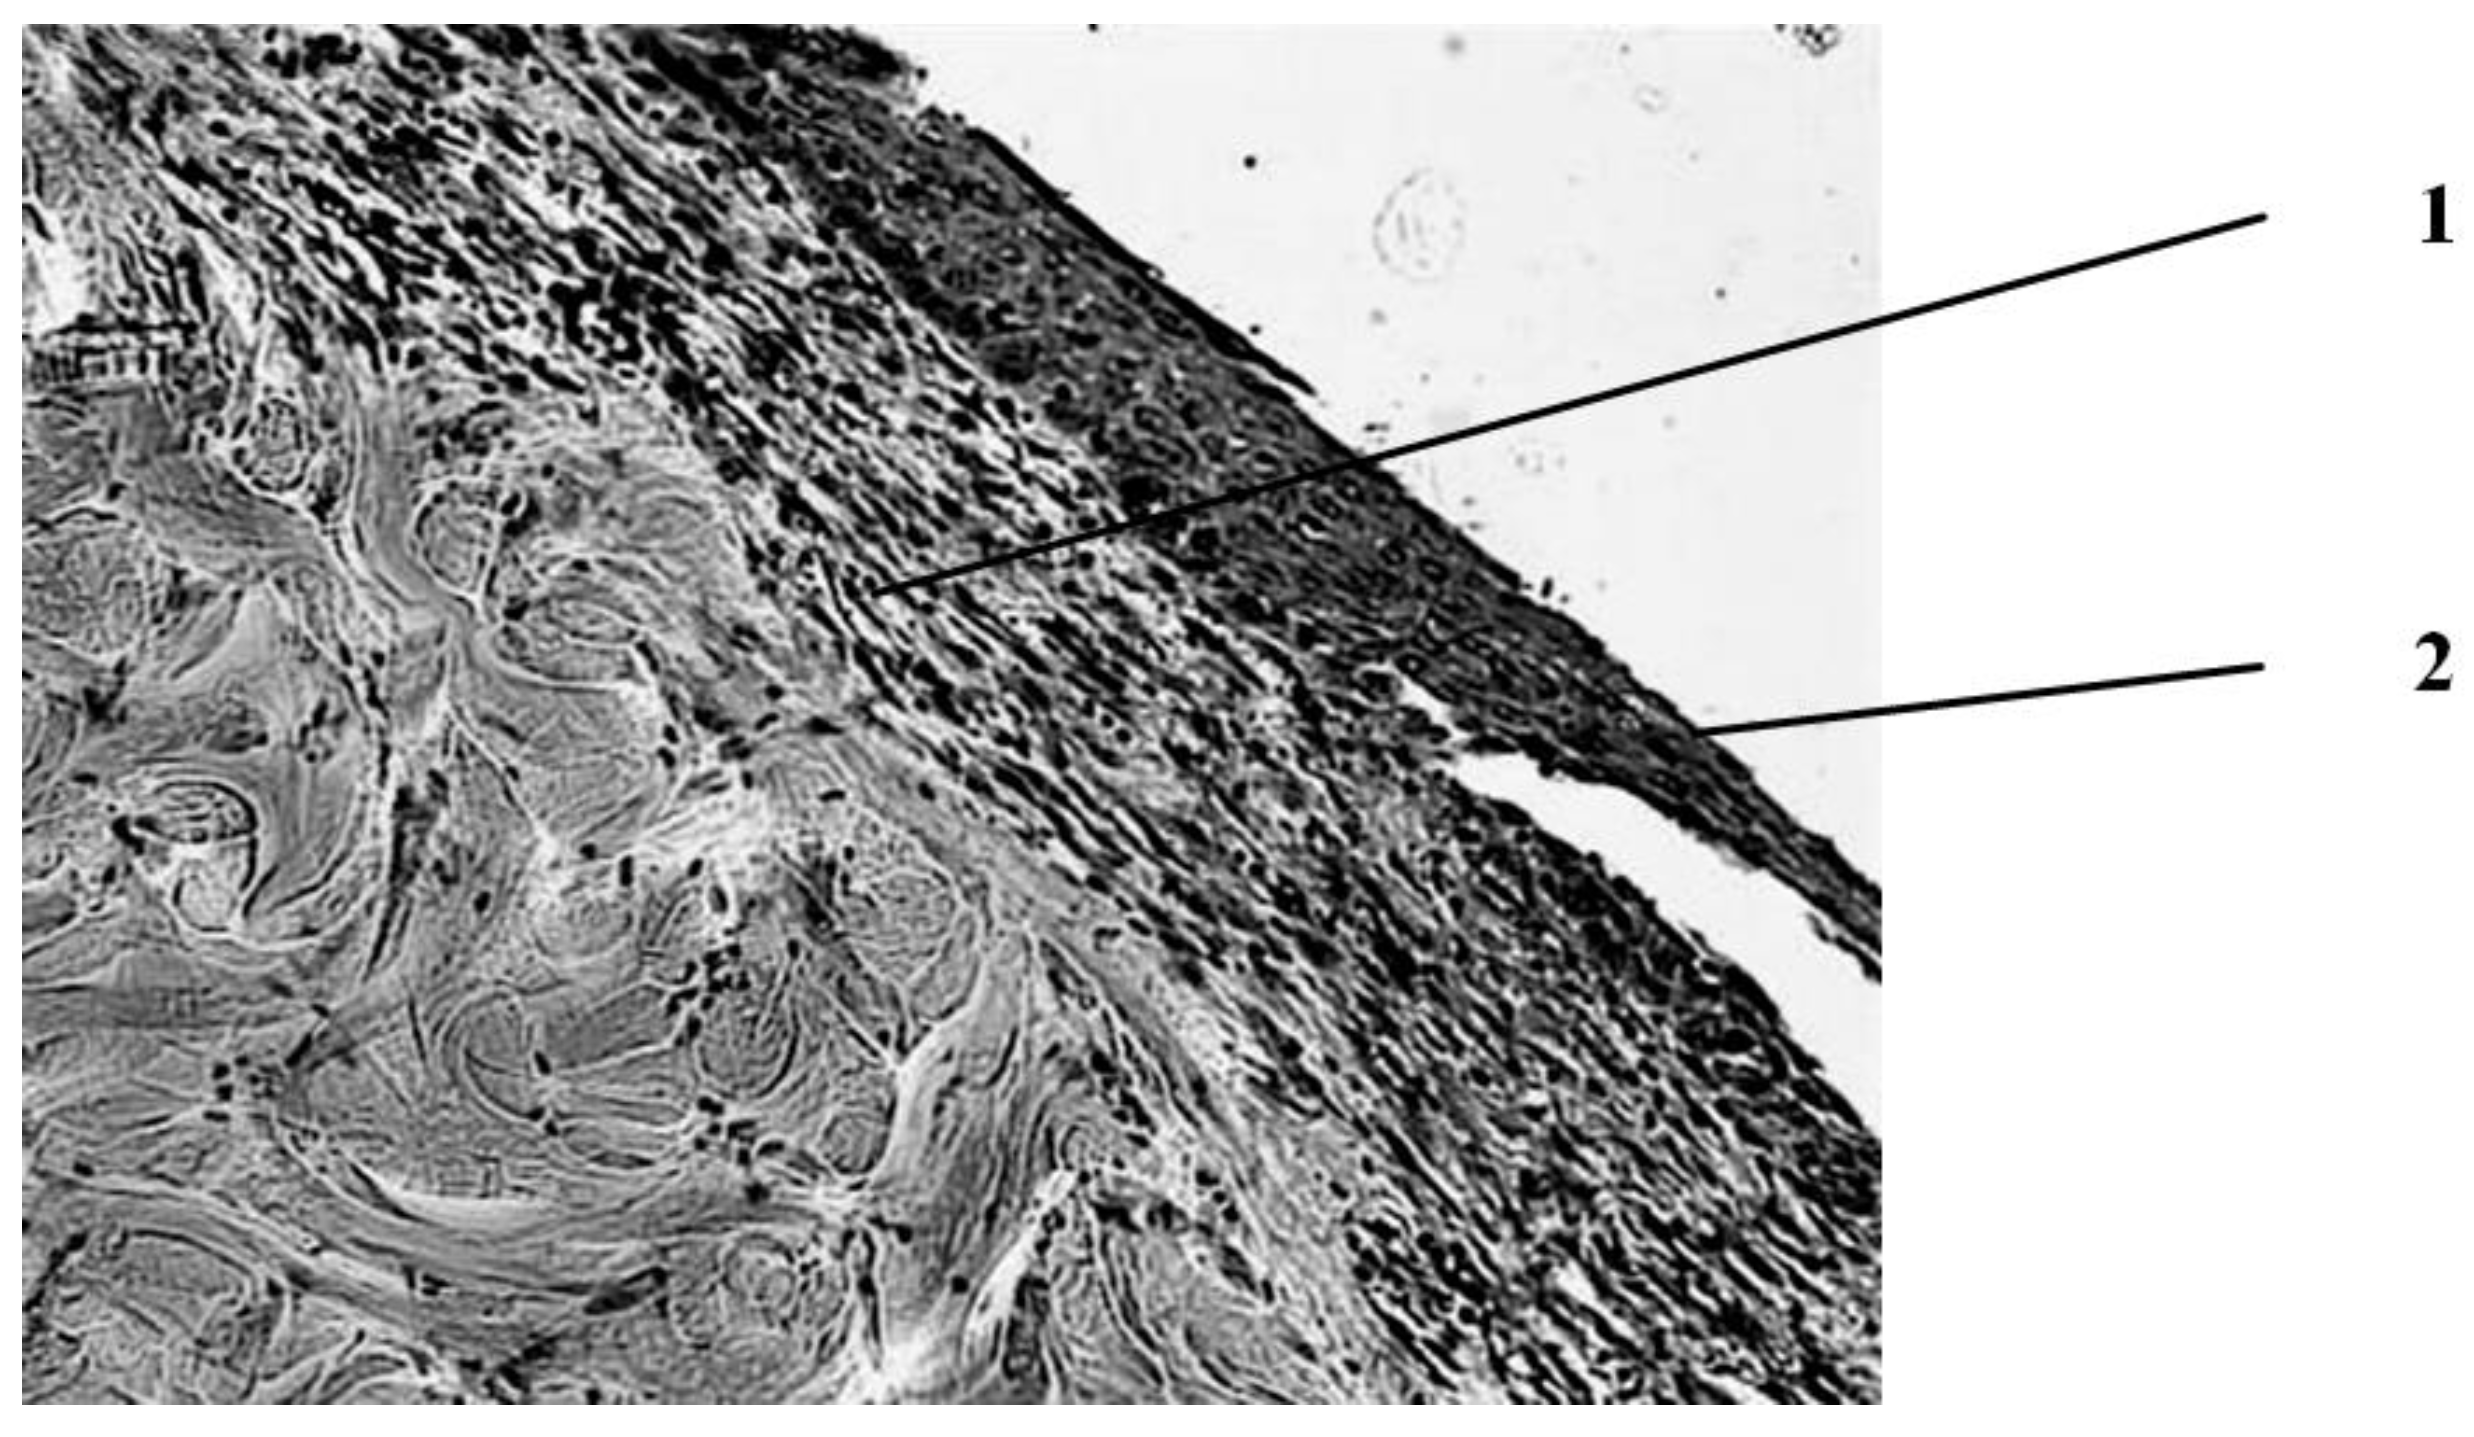

Seven days after the injury, in the group of animals whose wounds were treated with ozonated oil, purulent inflammation prevails, which is noted in the form of purulent exudate on the wound surface among the necrotic epidermis and under it, as well as in the form of focal purulent infiltrates in the necrotic dermis (Figure 3).

A continuous demarcation shaft is not formed, but, nevertheless, its placement in the dermis is indicated by leukocyte infiltrates located, albeit discretely, but at a short distance from each other. Individual leukocyte infiltrates occur at different depths of the necrotic dermis up to the skin’s own muscle. Against this background, the initial phenomena of marginal epithelialization of the skin are noted. The tongues of the epidermis proliferating from the edges of the wound are embedded under the scab, separating it from the rest of the dermis mass. Under the skin’s own muscle, there is also a pronounced proliferation of cells with large nuclei and basophilic cytoplasm. The predominant part of them has a fusiform shape (fibroblasts). There are newly formed thin-walled vessels containing red blood cells. There are single muscle buds in the muscle tissue.

Figure 3. Histological picture of the wound seven days after the application of the burn during treatment with ozonated oil. The scab is infiltrated in places by segmented leukocytes; clusters of microbial colonies are visible in it. Purulent exudate is determined under the scab. In the necrotic dermis—microabsesses. 1—scab. 2—purulent exudate. Stained with hematoxylin and eosin. magn. ×200.